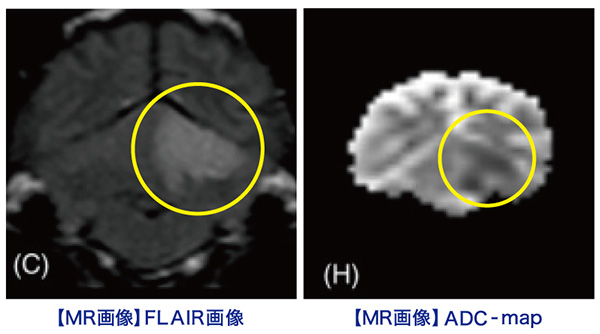

MRI所見

小脳右前小脳動脈領域にT2WI/FLAIR:高信号、DWI:高信号、ADC:一部低信号(部分的な拡散抑制を示唆)

→急性期小脳梗塞を強く疑う所見

この症例もやっぱり小脳中位核を含んでいます、瞳孔不同(右眼散瞳)があったに違いない!!

【MR画像】横断像 T2強調画像

【MR画像】横断像 T2強調画像

【MR画像】横断像 FLAIR画像

【MR画像】横断像 FLAIR画像

【MR画像】横断像 拡散強調画像

【MR画像】横断像 拡散強調画像

【MR画像】横断像 ADC-map

【MR画像】横断像 ADC-map